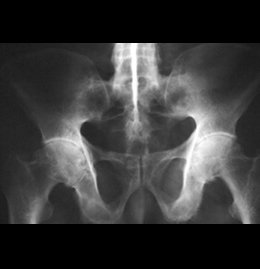

Gammagrafía Ósea Segmentaria

¿Le diagnosticaron sacroileitis?

¿Tiene dolores en la pélvis?

¿Tiene dolores en los hombros?

Este examen le puede ayudar.

Detalle técnico

Es un examen imagenológico que se usa para diagnosticar enfermedades óseas y averiguar su gravedad.

Gamma Ósea Osteoarticular DC/Sacroileitis